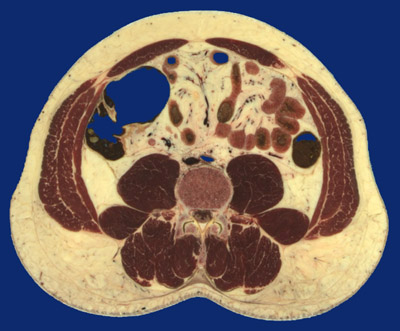

Identify the following regions in the image above: Linea alba - Rectus abdominus - External oblique - Internal oblique - Transversus abdominis - Sacrospinalis - Multifidus - Erector spinae muscle group (iliocostalis, longissimus dorsi, spinalis dorsi) - Psoas major - Quadratus lumborum - Ascending colon - Descending colon - Ileum - Descending aorta - Inferior vena cava - Vertebral body - Superior articular process - Inferior articular process - Apophyseal joint - Spinal canal with cauda equina - Thoracolumbar fascia